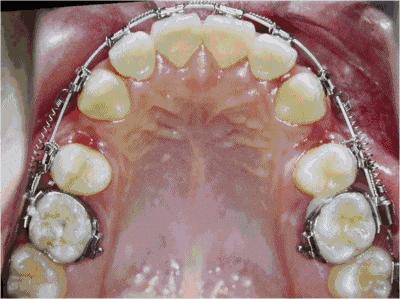

孩子换牙之后长出的新牙就是恒牙,伴随我们终生,恒牙早期阶段男孩女孩也不同,通常女孩子在11-14岁间,男孩子在13-15岁间,这个时期如果孩子牙齿问题比较严重的话,是矫正牙齿最好的阶段,恒牙已经萌生且基本固定,但恒牙早期阶段牙床还没有完全固定好,在继续发育生长,所以这个阶段在借助牙齿自身改建能力的基础上,通过医学手段矫正,有利于牙齿发育到最佳水平。